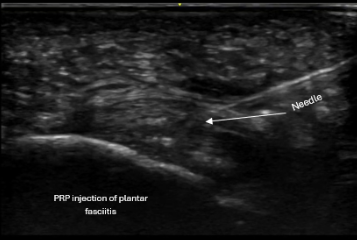

Ultrasound-guided PRP injection targeting plantar fascia pathology

Diagnostic Clarity Changes the Plan

Every evaluation begins with ultrasound paired with your functional complaints.

This allows us to:

• Distinguish inflammation from chronic degeneration

• Identify partial tearing

• Avoid unnecessary imaging

• Determine whether injection-based treatment is appropriate

Ultrasound also allows seamless transition into ultrasound-guided procedures when needed.

PRP (Platelet-Rich Plasma) (link to PRP page)

Often considered for:

• Chronic Achilles tendinopathy

• Partial tendon tears

• Chronic plantar fasciopathy

• Pain unresponsive to conservative care

All injections are performed using real-time ultrasound guidance to ensure precise placement into the area of pathology while protecting surrounding structures.